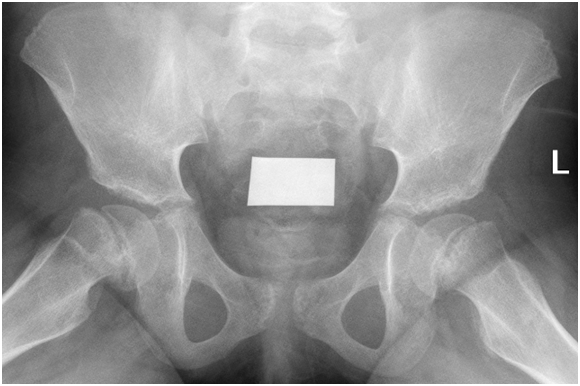

She has tiredness and fatigue and non-specific symptoms. She was treated with thyroxin and her thyroid functions test normalized in 2months time. After her improvement of thyroid functions test she developed limping and pain in her left leg which get worse with activity. We tested her bone profile and we found vitamin D deficiency so she received treatment for that. But in spite of improvement of the vitamin d deficiency and thyroid disease she continue to have the limping and pain in her leg so we referred her to orthopedics. The orthopedic did for her pelvic AP x-ray and found Bilateral symmetrical slipped capital proximal femoral epiphyses are noted with metaphyseal sclerosis and irregularity. The proximal femoral epiphyses are of normal density and contour Unremarkable acceptable in both sides. So she was treated surgically and cannulated screw fixation was done in both hip joints. After that the patient improved regarding limping and pain and without complaints.

In this case we present that after treatment of the sever hypothyroidism the symptoms of masked SCFE appears indicating that evaluations of thyroid function test is strongly recommended in cases of SCFE (Figures 1‒3).

Figure 1 Slipped capital femoral epiphysis (SCFE) is an important hip disorder of adolescence commonly occurring between the ages of 8–15years.